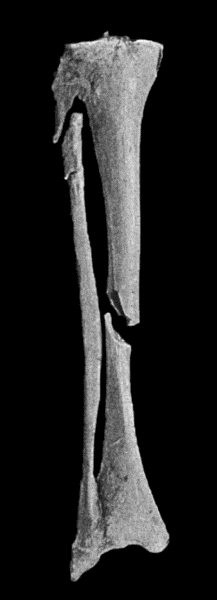

5 3.Oblique Fracture of Tibia; with partial Separation of Epiphysis of Upper End of Fibula; and Incomplete Fracture of Fibula in Upper Third

(2) According to the Direction of the Break.—Transverse fractures are those in which the bone gives way more or less exactly at right angles to its long axis. These usually result from direct violence or from end-to-end pressure. Longitudinal fractures extending the greater part of the length of a long bone are exceedingly rare. Oblique fractures are common, and result usually from indirect violence, bending, or torsion (Fig. 3). Spiral fractures result from forcible torsion of a long bone, and are met with most frequently in the tibia, femur, and humerus.